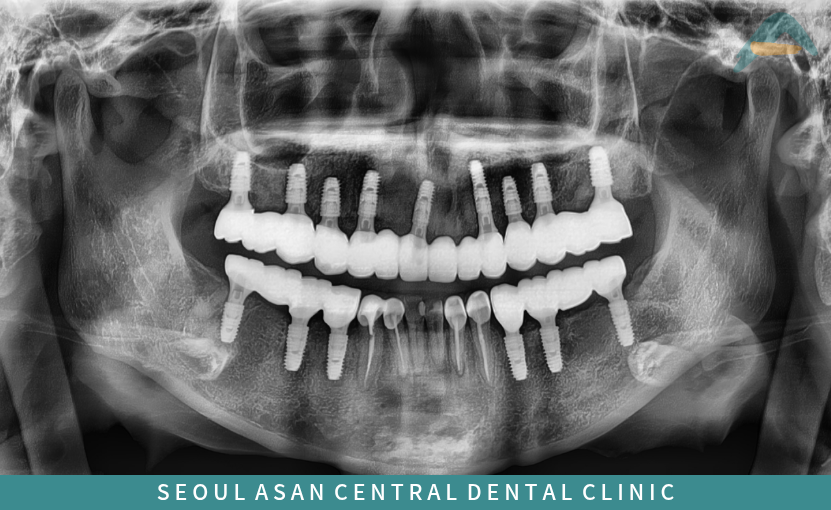

반면 성남치과 임플란트는

인공치근을 잇몸뼈에 직접 식립하여

단단하게 고정하는 치료 방법으로,

자연치아에 가까운 구조를 가지고 있어

저작력을 약 80% 이상 회복할 수 있으며

심미성 또한 우수한데요.

이를 위해 성남치과는 파노라마 촬영과 3D CT 등

디지털 영상 장비를 활용하여

눈에 보이지 않는 내부 구조를 면밀히 확인하고,

임플란트 식립 가능 여부를 객관적으로 판단하게 됩니다.

또한 식립이 가능하다고 판단될 경우에는

적절한 위치 선정과 함께

Fixture의 굵기와 길이,

식립 각도 등을 사전에 시뮬레이션하여

기능적·해부학적 안전성을 충분히 고려해야 합니다.